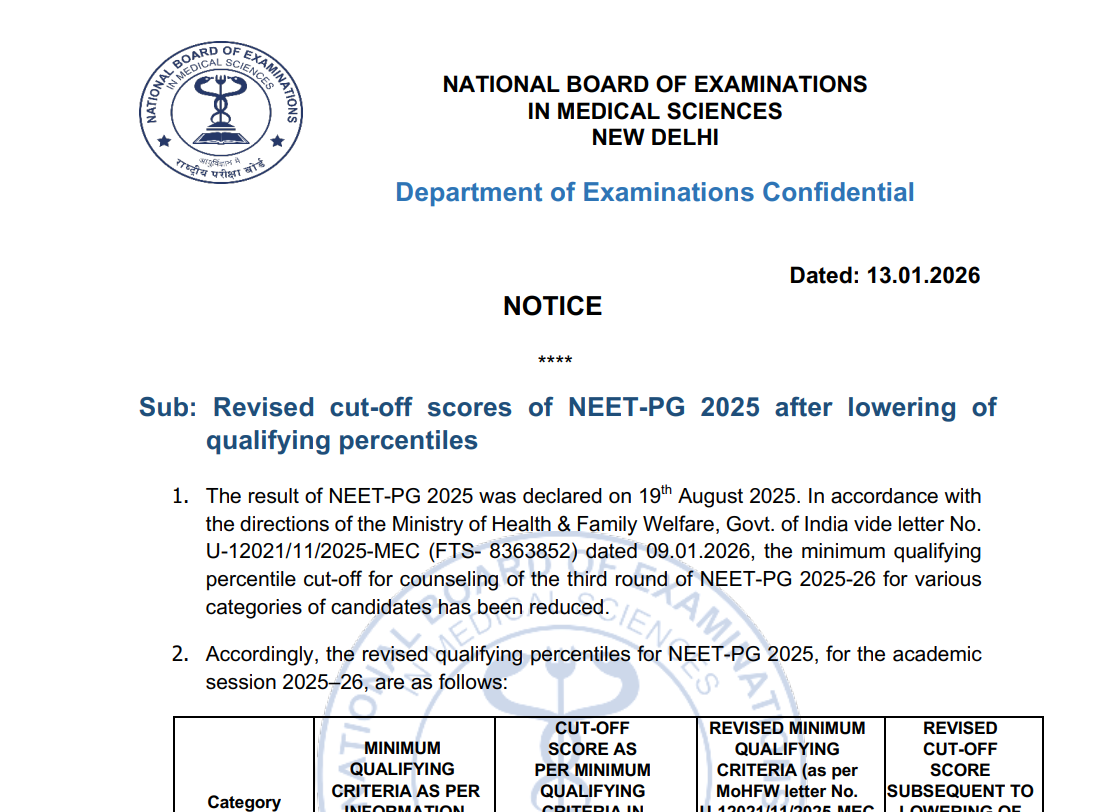

SC turns down plea to stay NEET counselling

2025-07-24